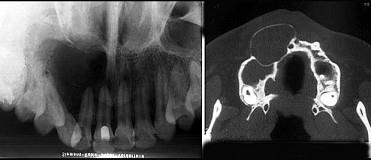

位于上颌侧切牙与尖牙之间的非牙源性囊肿(影像检查如图)是()A.球上颌囊肿B.鼻腭囊肿C.正中囊肿D.鼻唇囊肿E.角化囊肿

问题 位于上颌侧切牙与尖牙之间的非牙源性囊肿(影像检查如图)是()

选项 A.球上颌囊肿 B.鼻腭囊肿 C.正中囊肿 D.鼻唇囊肿 E.角化囊肿

答案 A